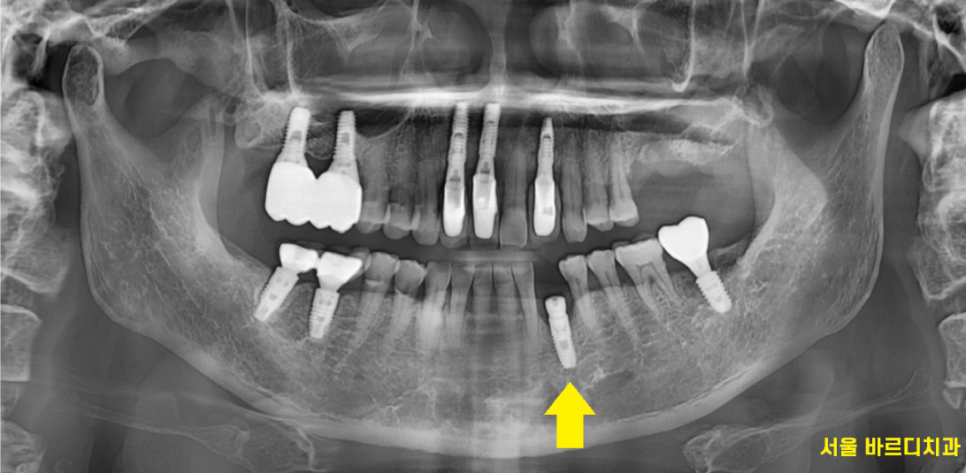

24.04.26

심미성이 요구되는 앞니 임플란트 수술을 할때

주로 이 방법을 사용하는데요.

3d ct를 통해 분석

뼈가 충분한 곳에 명일동 임플란트를 심고

기계를 통해 뼈랑 얼마나 잘 붙었는지

확인하였을때

▼명일동 치과 하루 임플란트 결과▼

80 이상 수치가 나오면

내 뼈와 잘 붙은겁니다.

환자분도 81/80

두곳에서 수치를 재어보았을 때

80이상이 나와서 뽄을 떴습니다.

(수술 당일 측정)